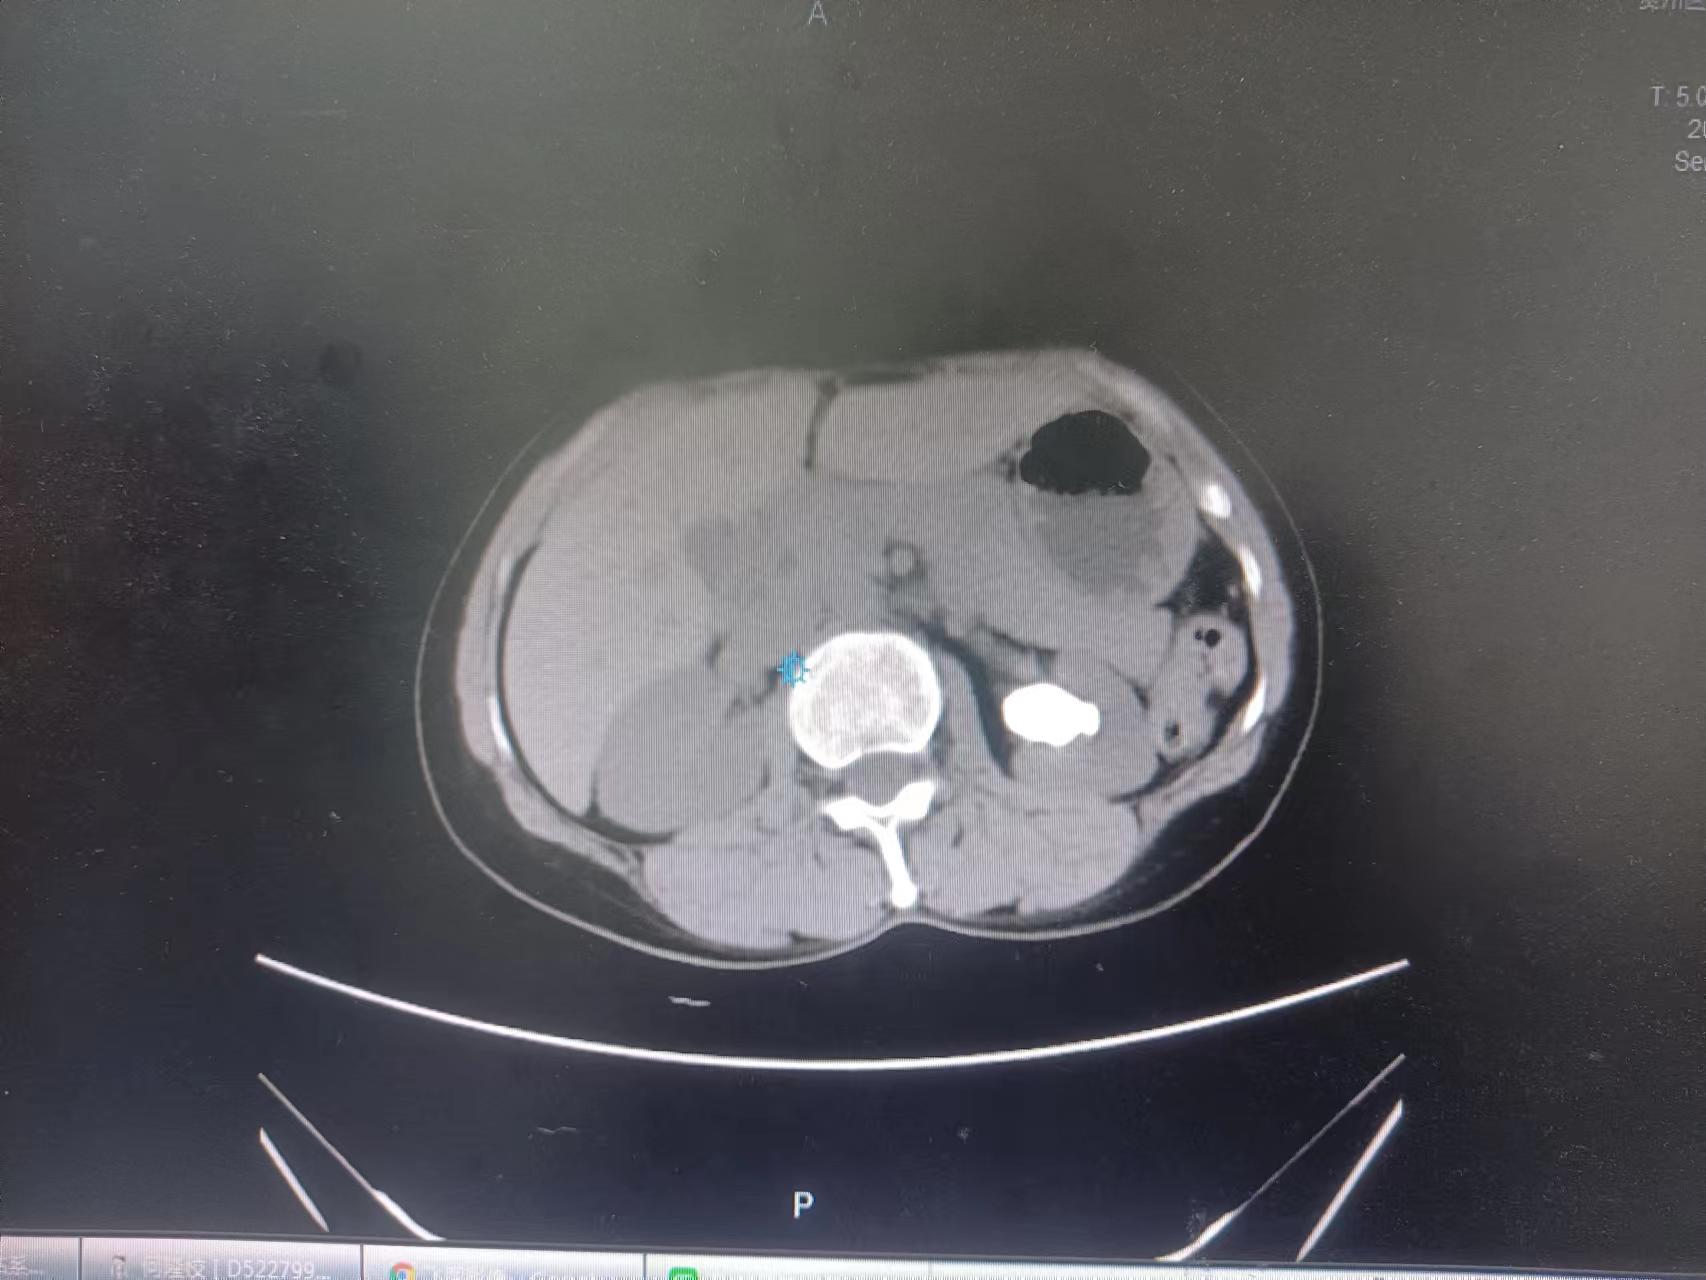

术前

入院后,泌尿外科副主任雷鸣带领团队认真分析,决定为李爷爷行经尿道输尿管软镜钬激光碎石取石术。该手术方式不用开刀,经过人体自然腔道直接到肾,做到无死角碎石取石。